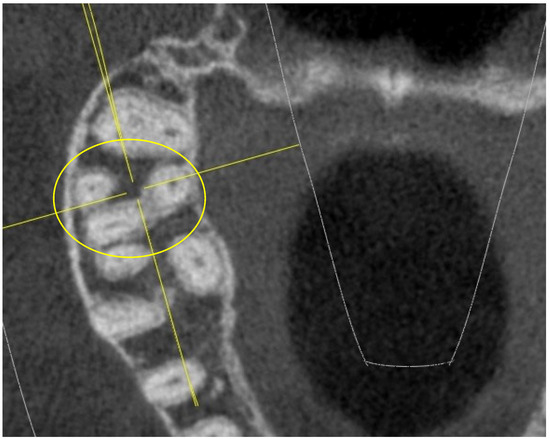

Upper First and Second Molar Pulp Chamber Endodontic Anatomy Evaluation According to a Recent Classification: A Cone Beam Computed Tomography Study

2. Materials and Methods

- long and short diameter of the pulp chamber floor;

- shape of the pulp chamber associated with a letter of the alphabet (in relation to the number and arrangement of canal orifices);

- diameter of root canal orifices;

- distance between intra- and inter-root canals;

- possible fusion of the roots;

- root diameter.

- K: in maxillary molars with the presence of four canal orifices: MB, MB-2, disto-buccal and palatal; a line joining the disto-buccal and palatal and two other lines radiating from the center of this line to MB and MB-2, forming the letter “K” of the alphabet.

- Y: in maxillary molars with three canal orifices: MB, disto-buccal and palatal; when a line is formed joining the three canals in the center of the access cavity, it resembles the letter “Y” of the alphabet.